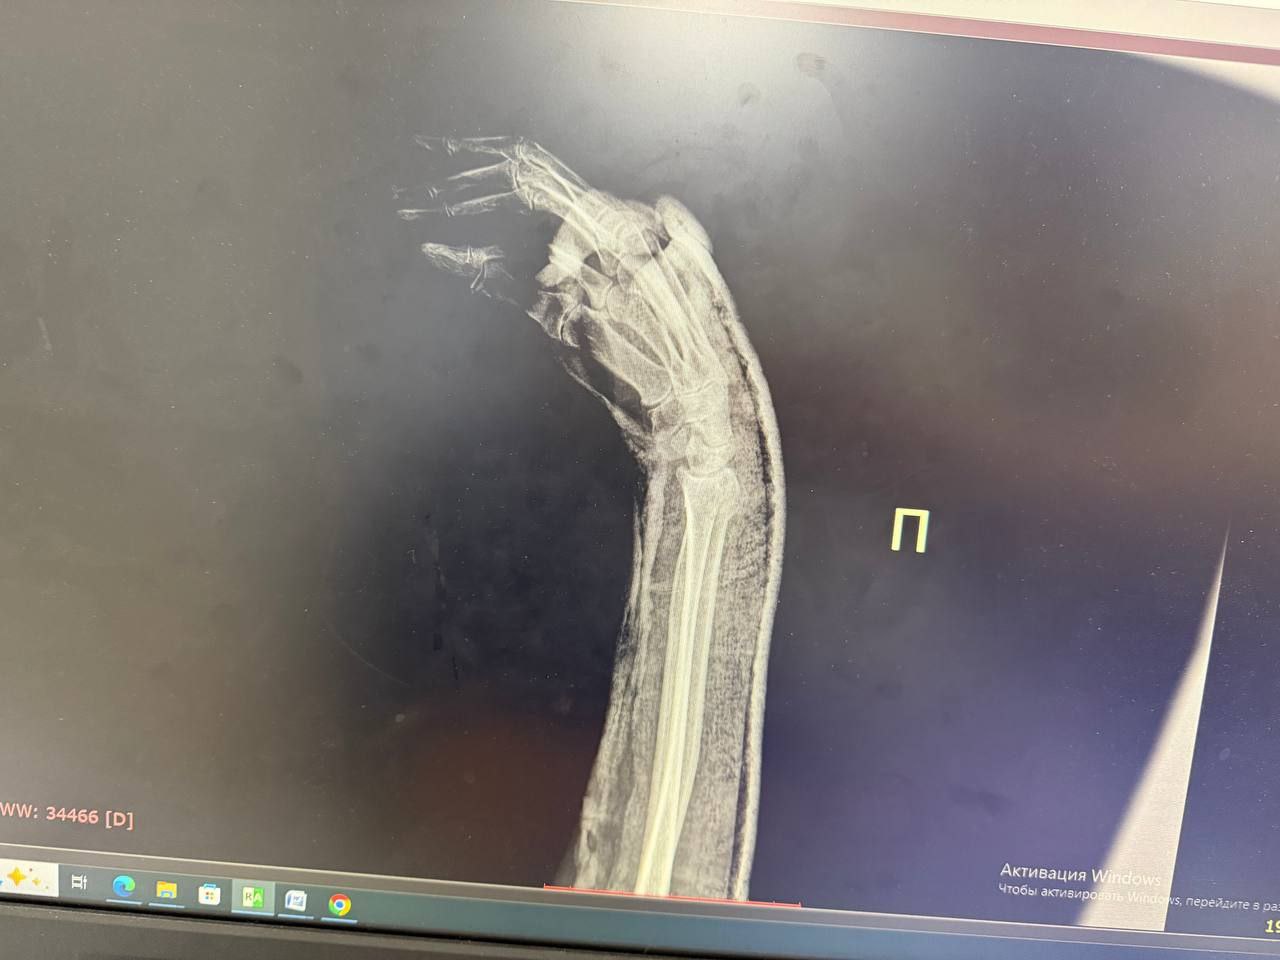

Чаще в таких случаях страдают голеностопный и лучезапястный суставы, рассказал нашей съёмочной группе врач травматолог-ортопед городской больницы №2 Белгорода Александр Шахов.